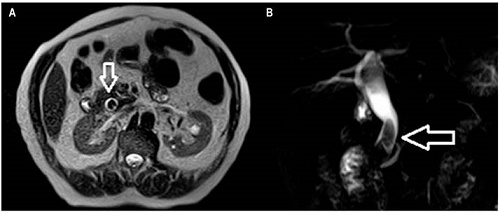

Así pues, el paciente fue valorado por el servicio de gastroenterología, con sospecha de coledocolitiasis. Por tanto, se solicitó una colangiorresonancia magnética (CRM), cuyo resultado (enero 2 de 2019) describió la presencia de 2 cálculos facetados de 16 y 18 mm, con una dilatación del colédoco distal de hasta 17 mm y una leve dilatación de la vía biliar intrahepática (Figura 1).